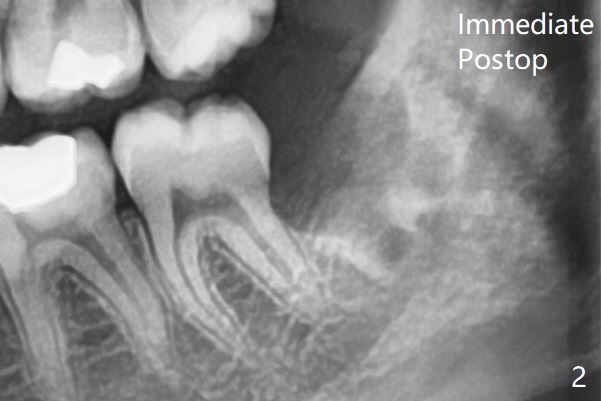

16岁智齿     Last     Next